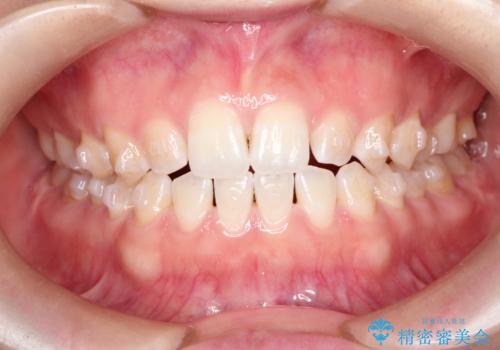

前歯の隙間を閉じたい インビザラインによる矯正

- 上下の前歯に隙間があるとのことで来院されました。

インビザラインにて隙間を閉じる矯正を行いました。